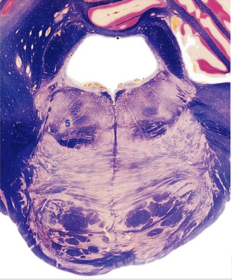

| Hypoglossal nucleus | |

| Hypoglossal nerve | |

| Dorsal motor nucleus of X | |

| Nucleus ambiguus | |

| Solitary tract | |

| Solitary nucleus | |

| ALS | |

| Medial lemniscus | |

| Medial longitudinal fasciculus | |

| Spinal tract of V | |

| Spinal nucleus of V | |

| Lateral (external, accessory) cuneate nucleus | |

| Medullary pyramids | |

| Anterior spinocerebellar tract | |

| CN IX | |

| Inferior cerebellar peduncle | |

| Inferior olivary complex | |

| Dorsal cochlear nucleus | |

| Inferior vestibular nucleus | |

| Medial vestibular nucleus | |